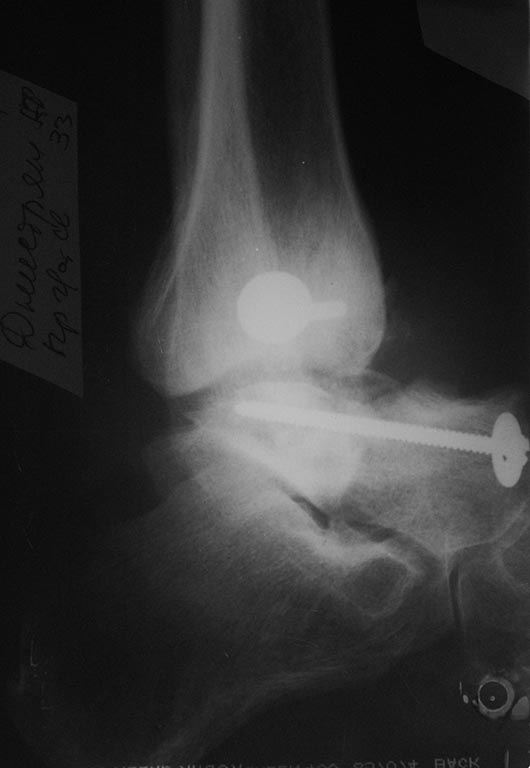

[Ortho] Последствия переломовывиха таранной кости

Извините "корявые" руки травматолога и нет не дружат:). Выкладываю

первичный снимок. Если можно более конкретно методики артродезов. Делали

все кроме стержня. И основной вопрос как определить границу

жизнеспособной таранной кости???